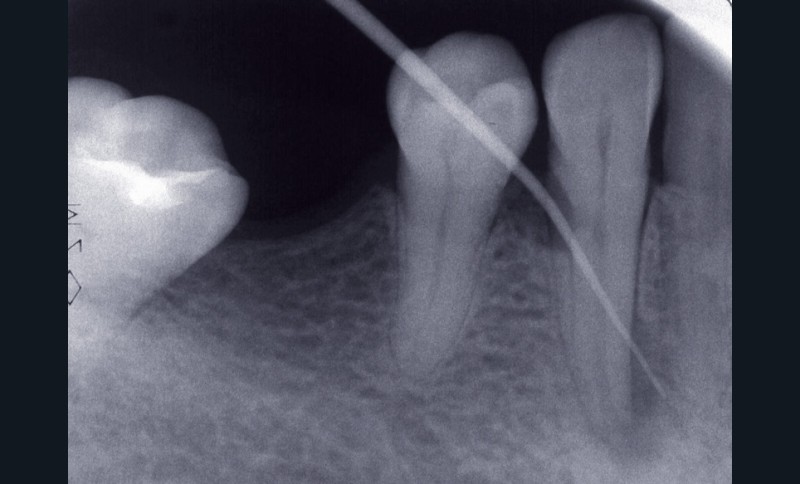

La première consiste en la persistance d’une infection intraradiculaire au sein de la zone apicale d’un canal riche en ramifications et en canaux accessoires ou d’un canal oublié (fig. 4) :

ces infections sont caractérisées par une flore microbienne particulièrement résistante correspondant aux micro- organismes résiduels à la suite d’une infection primaire ou secondaire. Ces micro-organismes sont généralement présents sous forme d’un biofilm au sein duquel ces derniers, noyés dans une matrice polysaccharidique adhérente aux parois canalaires [3], sont significativement plus résistants que ceux simplement en suspension [48]. Ils peuvent dès lors résister aux diverses solutions d’irrigation et médicaments intracanalaires, mais également survivre dans un environnement nutritionnel restreint [2, 5, 47]. Lors de la mise en forme canalaire, certaines régions, du fait de la complexité anatomique des racines, ne peuvent être ni débridées mécaniquement ni obturées. Ainsi, des colonies bactériennes sous forme de biofilm sont fréquemment retrouvées dans les ramifications apicales, dans les isthmes et au sein de concavités inaccessibles de la paroi radiculaire [19]. Ces zones représentent des niches de colonisation bactérienne pouvant par la suite contrarier la guérison apicale. Les micro-organismes retrouvés sont principalement Enterococcus faecalis et Candida albicans [41], même si d’autres espèces, plus généralement retrouvées dans les infections primaires comme Propionibacterium, ont été également mises en évidence [30, 32].